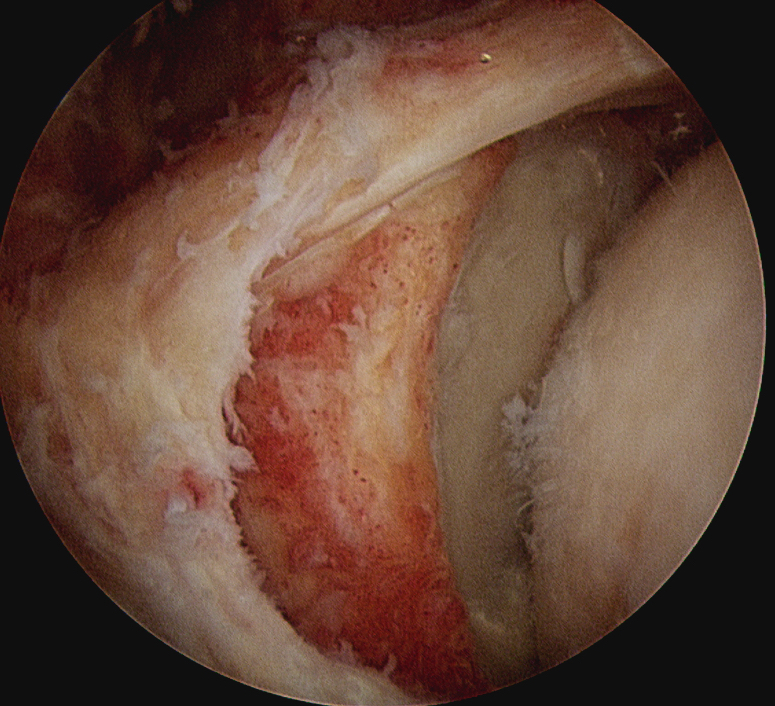

Subacromial arthroscopy

- typically leave area of humeral head exposed

True partial repair of the rotator cuff with exposed triangle of greater tuberosity